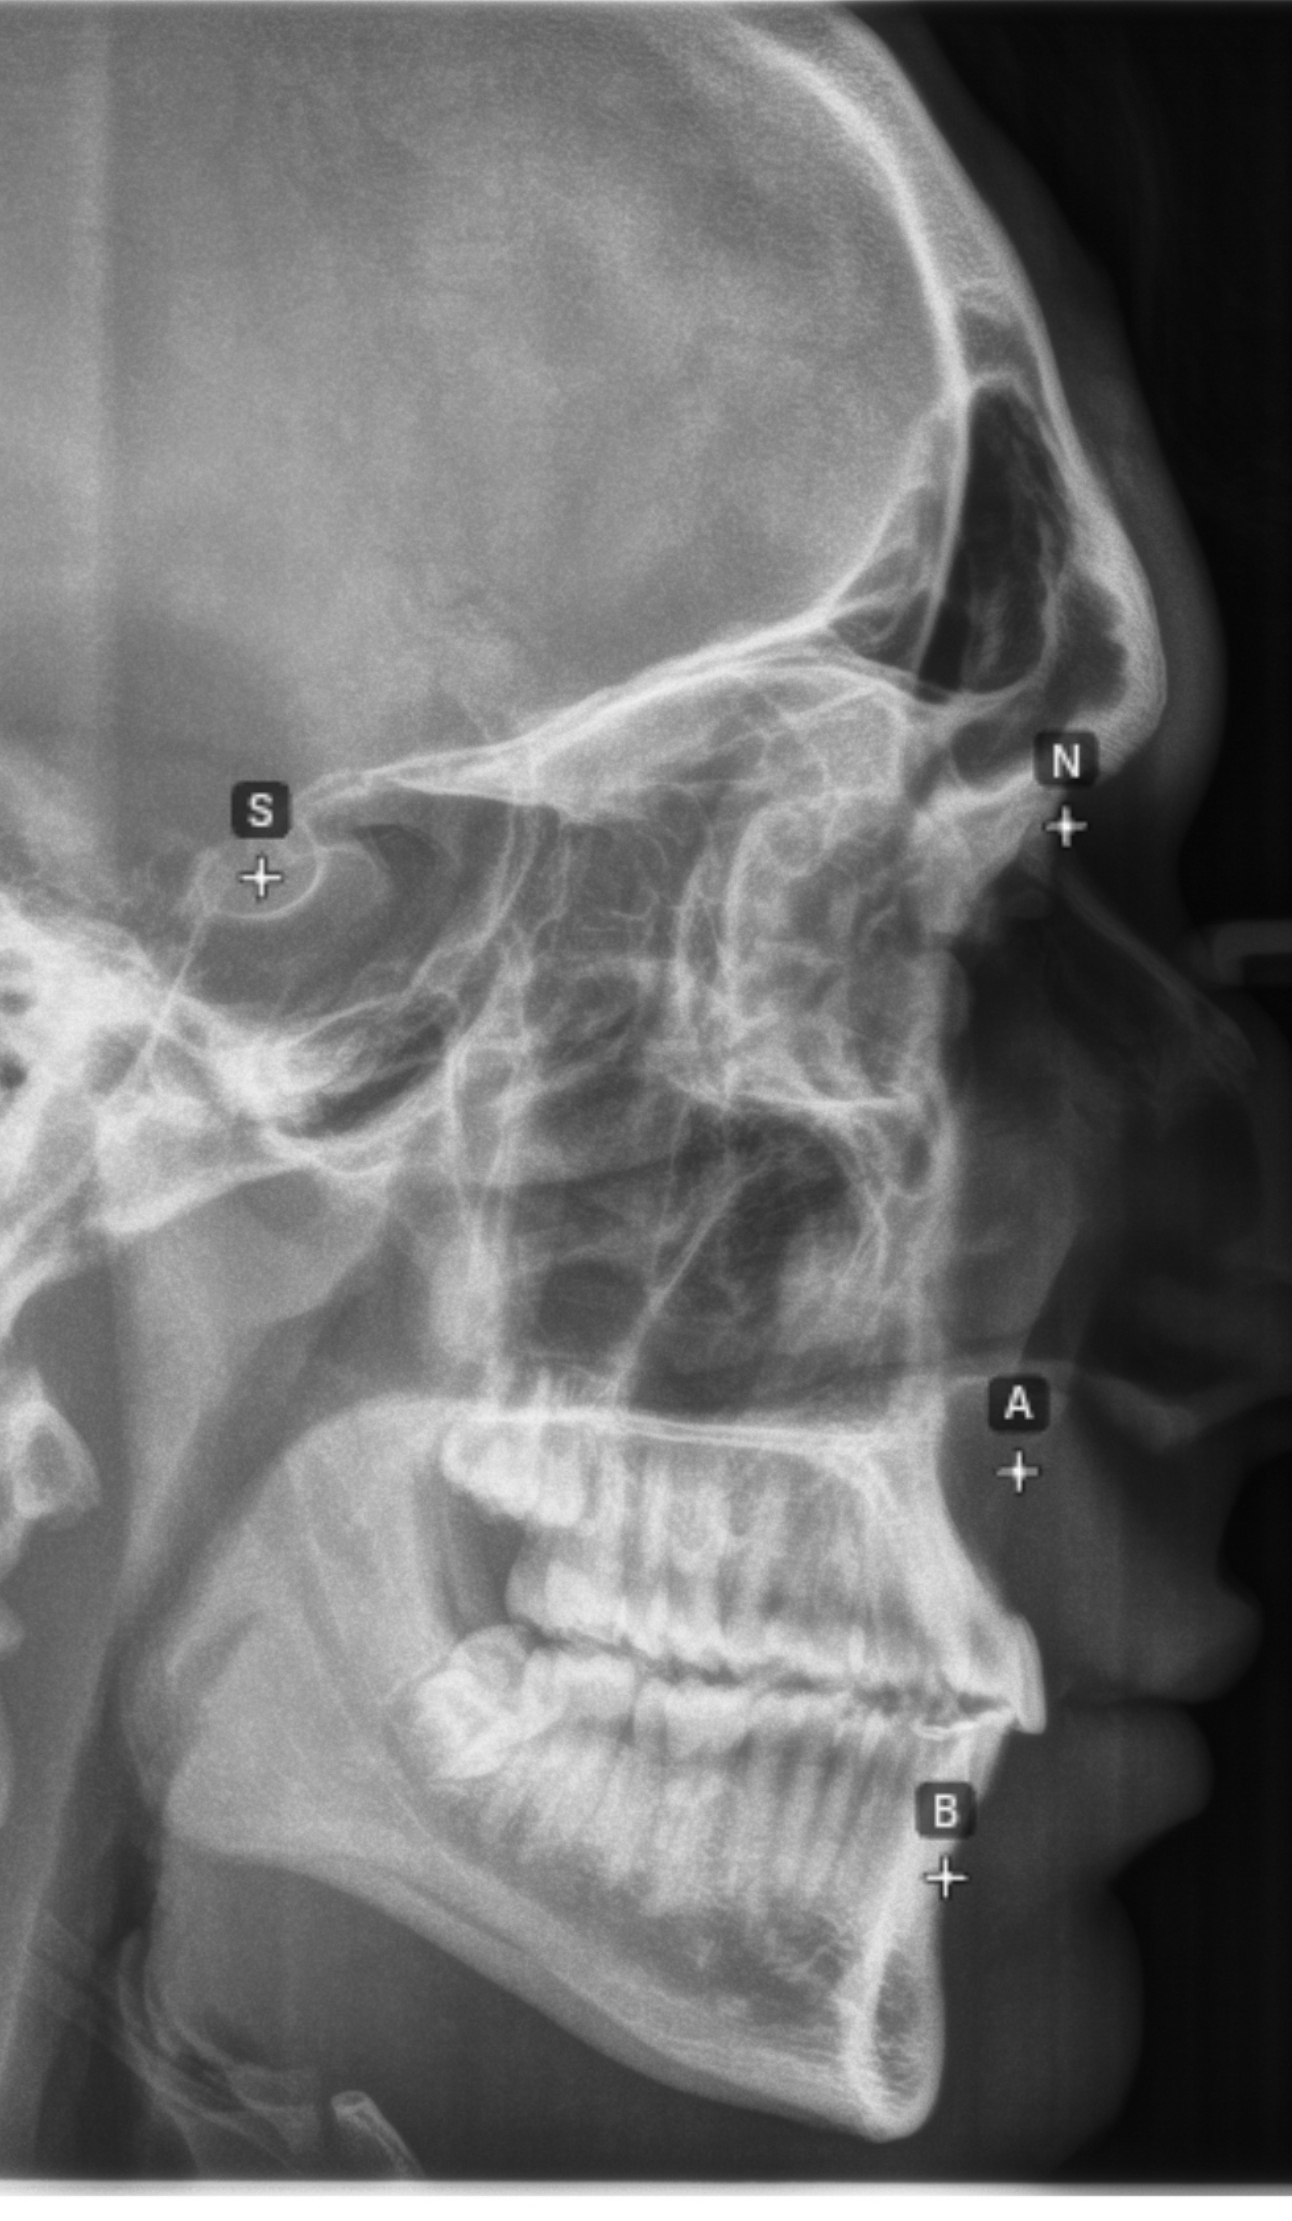

CBCT RENDERS

All attached. Frontal bone, left lateral, right lateral, soft tissue overlays, volume renders at different thresholds. The full skull, nothing hidden, nothing frauded with angles. You can see every problem I just described for yourself.

CBCT RENDERS

All attached. Frontal bone, left lateral, right lateral, soft tissue overlays, volume renders at different thresholds. The full skull, nothing hidden, nothing frauded with angles. You can see every problem I just described for yourself.